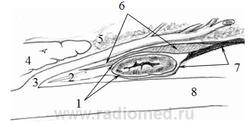

Рисунок 2.8 Связка нижнегоризонтальной ветви ДПК

1 - правая порция связки нижне-горизонтальной ветви ДПК

2 – нижнегоризонтальная ветвь ДПК

3 - нисходящая ветвь ДПК

4 - верхняя брыжеечная артерия

5 - связка Трейтца

6 - дуоденоеюнальный переход

7 - корень брыжейки тонкой кишки

8 - левая порция связки нижне-горизонтальной ветви ДПК